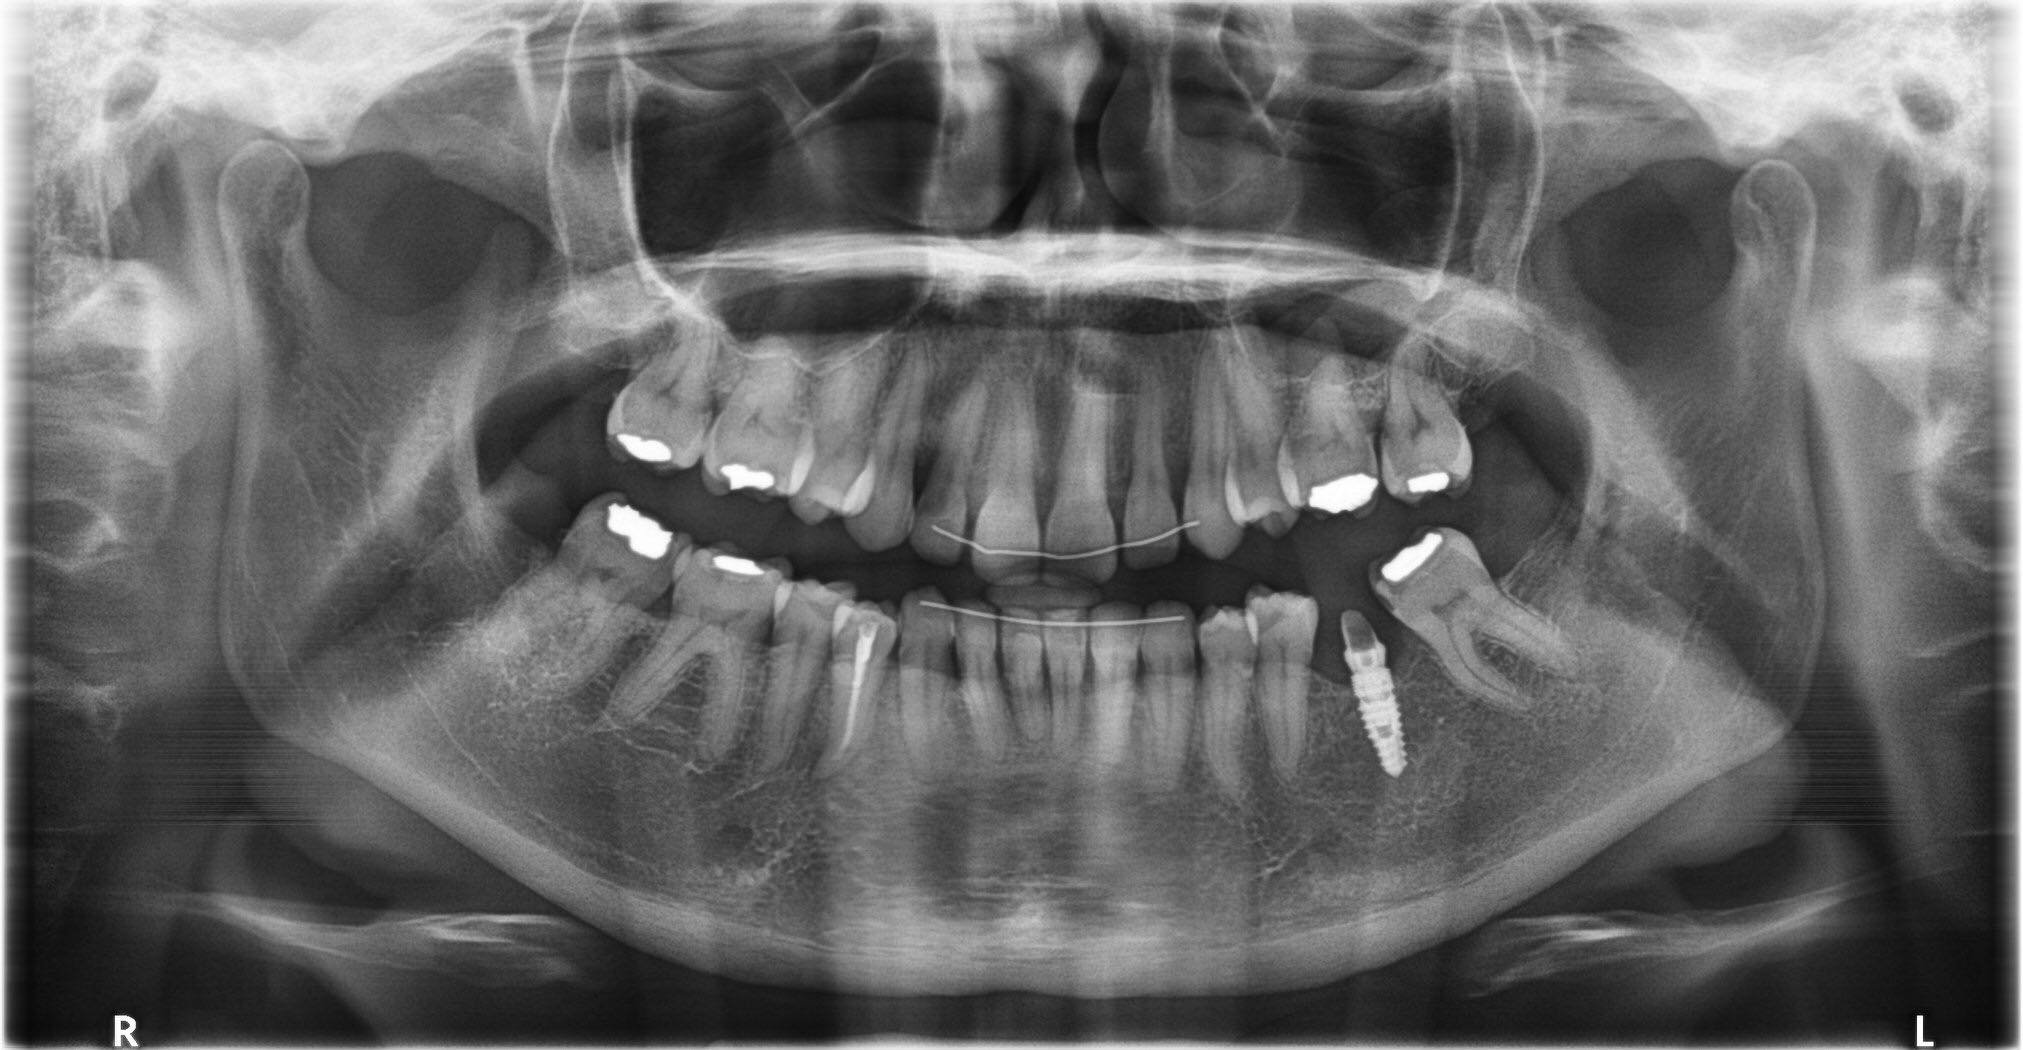

Je commence ci joint la pano

je sais juste que l'implant date d'environ 5 ans; la personne ne se rappelle pas qui lui a fait.

l'implant est conique, le col a des micros filets, l'apex est pointu, et la connexion est interne.

pour moi c'est un tiologic dentaurum....

je pense pas que ça soit un dentaurum

le tiologic à une spire dédoublée et le tiolox n'a pas de microspire au col.

sur la radio la spire est simple et le col est microspiré

je me demande si c'est pas un paltop